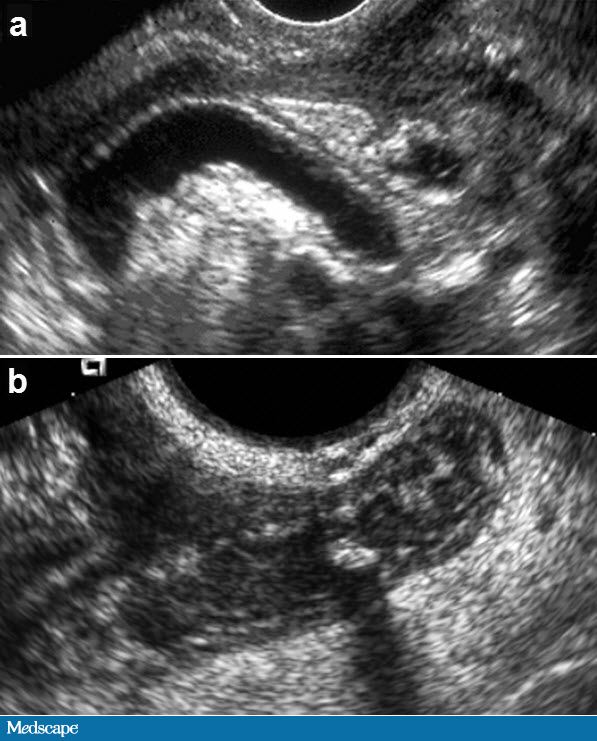

The first is that all patients with right lower quadrant pain do not necessarily have appendicitis, and actually have a normal appendix (Figure 1A, 1B). This surgery with removal of a normal appendix is a negative outcome; the patient has morbidity associated with that surgical procedure, and it does not look after the actual cause of their pain.

Figure 1. Normal appendix. a, long-axis image and b, cross-sectional image, show the normal appendix (A) arising from the basis of the cecum (C). The appendix shows a gut signature, a blind end, and diameter 6 mm or less. From Wilson SR. The gastrointestinal tract. In: Rumack CM, Wilson SR, Charboneau JW, Levine D, eds.Diagnostic Ultrasound. 4th ed. Philadelphia, Pa: Elsevier; 2010. Reproduced with permission.